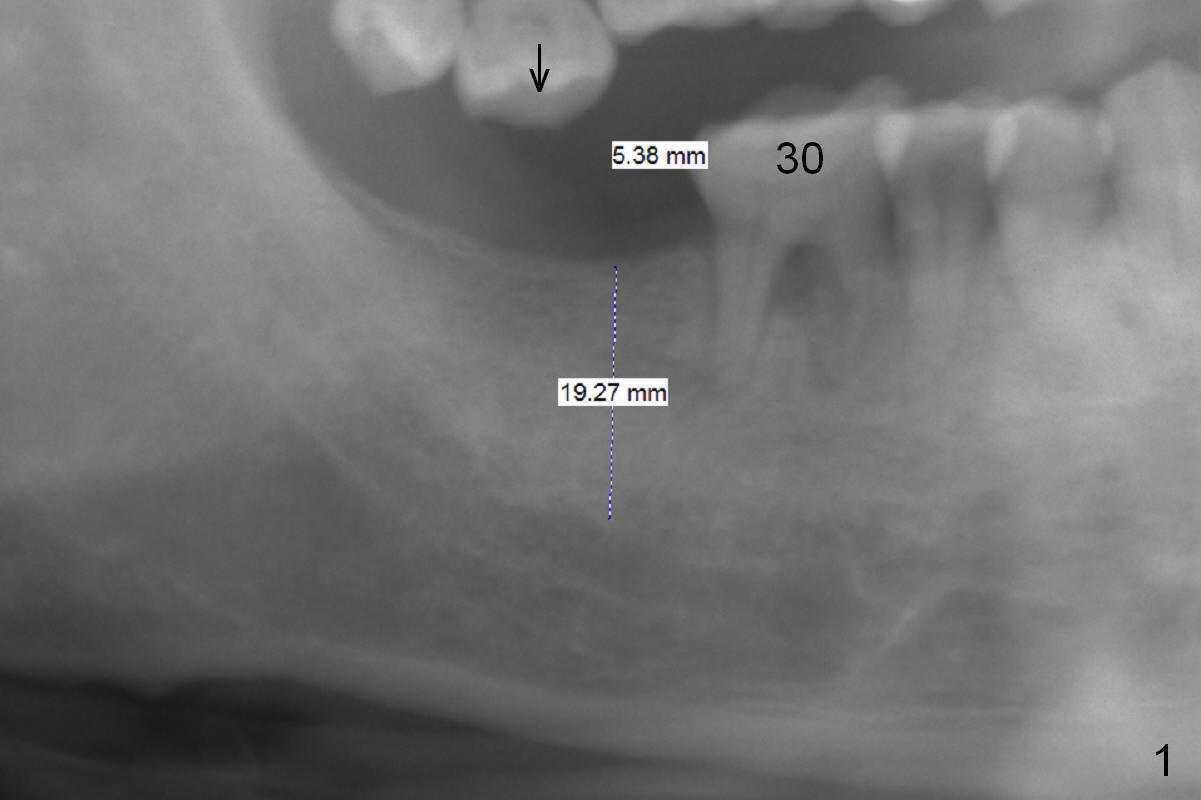

A 59-year-old man will return for #31 implant placement following #13 and 15 ones. Since the bone density in the original socket seems to be low, start osteotomy with 1.2 mm drill (flapless), followed by DIO bone expanders as deep as possible. When initial intraop PA is taken, measure the thickness of the gingiva. Since the implants on the left side were placed recently and the tooth #2 is supraerupted (arrow), achieving high stability at #31 is priority. A long implant is an easy choice. Prepare 18 mm drills. Take BW to confirm that the implant is placed subcrestally, if necessary. A healing abutment is most likely placed to reduce postop micro-movement.